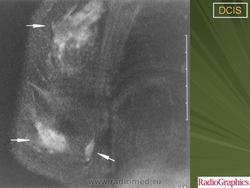

Обычно, ПКИС никак не проявляется и не выявляется при физикальном исследовании. Однако у небольшого числа женщин может отмечаться опухолевидное образование либо какие-то выделения из соска. Чаще всего протоковая карцинома выявляется на маммографии. Дело в том, что «старые» раковые клетки отмирая, не успевают полностью утилизироваться. В результате этого эта область пропитывается солями кальция (так называемое обызвествление) – образуются микрокальцинаты. Эти микрокальцинаты как раз и выявляются на маммограмме. В случае если полученные результаты маммографии врач считает подозрительными на рак, проводится следующий этап диагностики – биопсия.

Часто на маммограммах в области опухоли выявляются микрокальцинаты, что связано с том, что в опухоли происходит омертвление ее клеток (некроз), которые в последствие пропитываются солями кальция. Опухоль при инвазивной карциноме может быть различных размеров, и у клеток может быть различное время деления, так что некоторые клетки растут быстрее других.